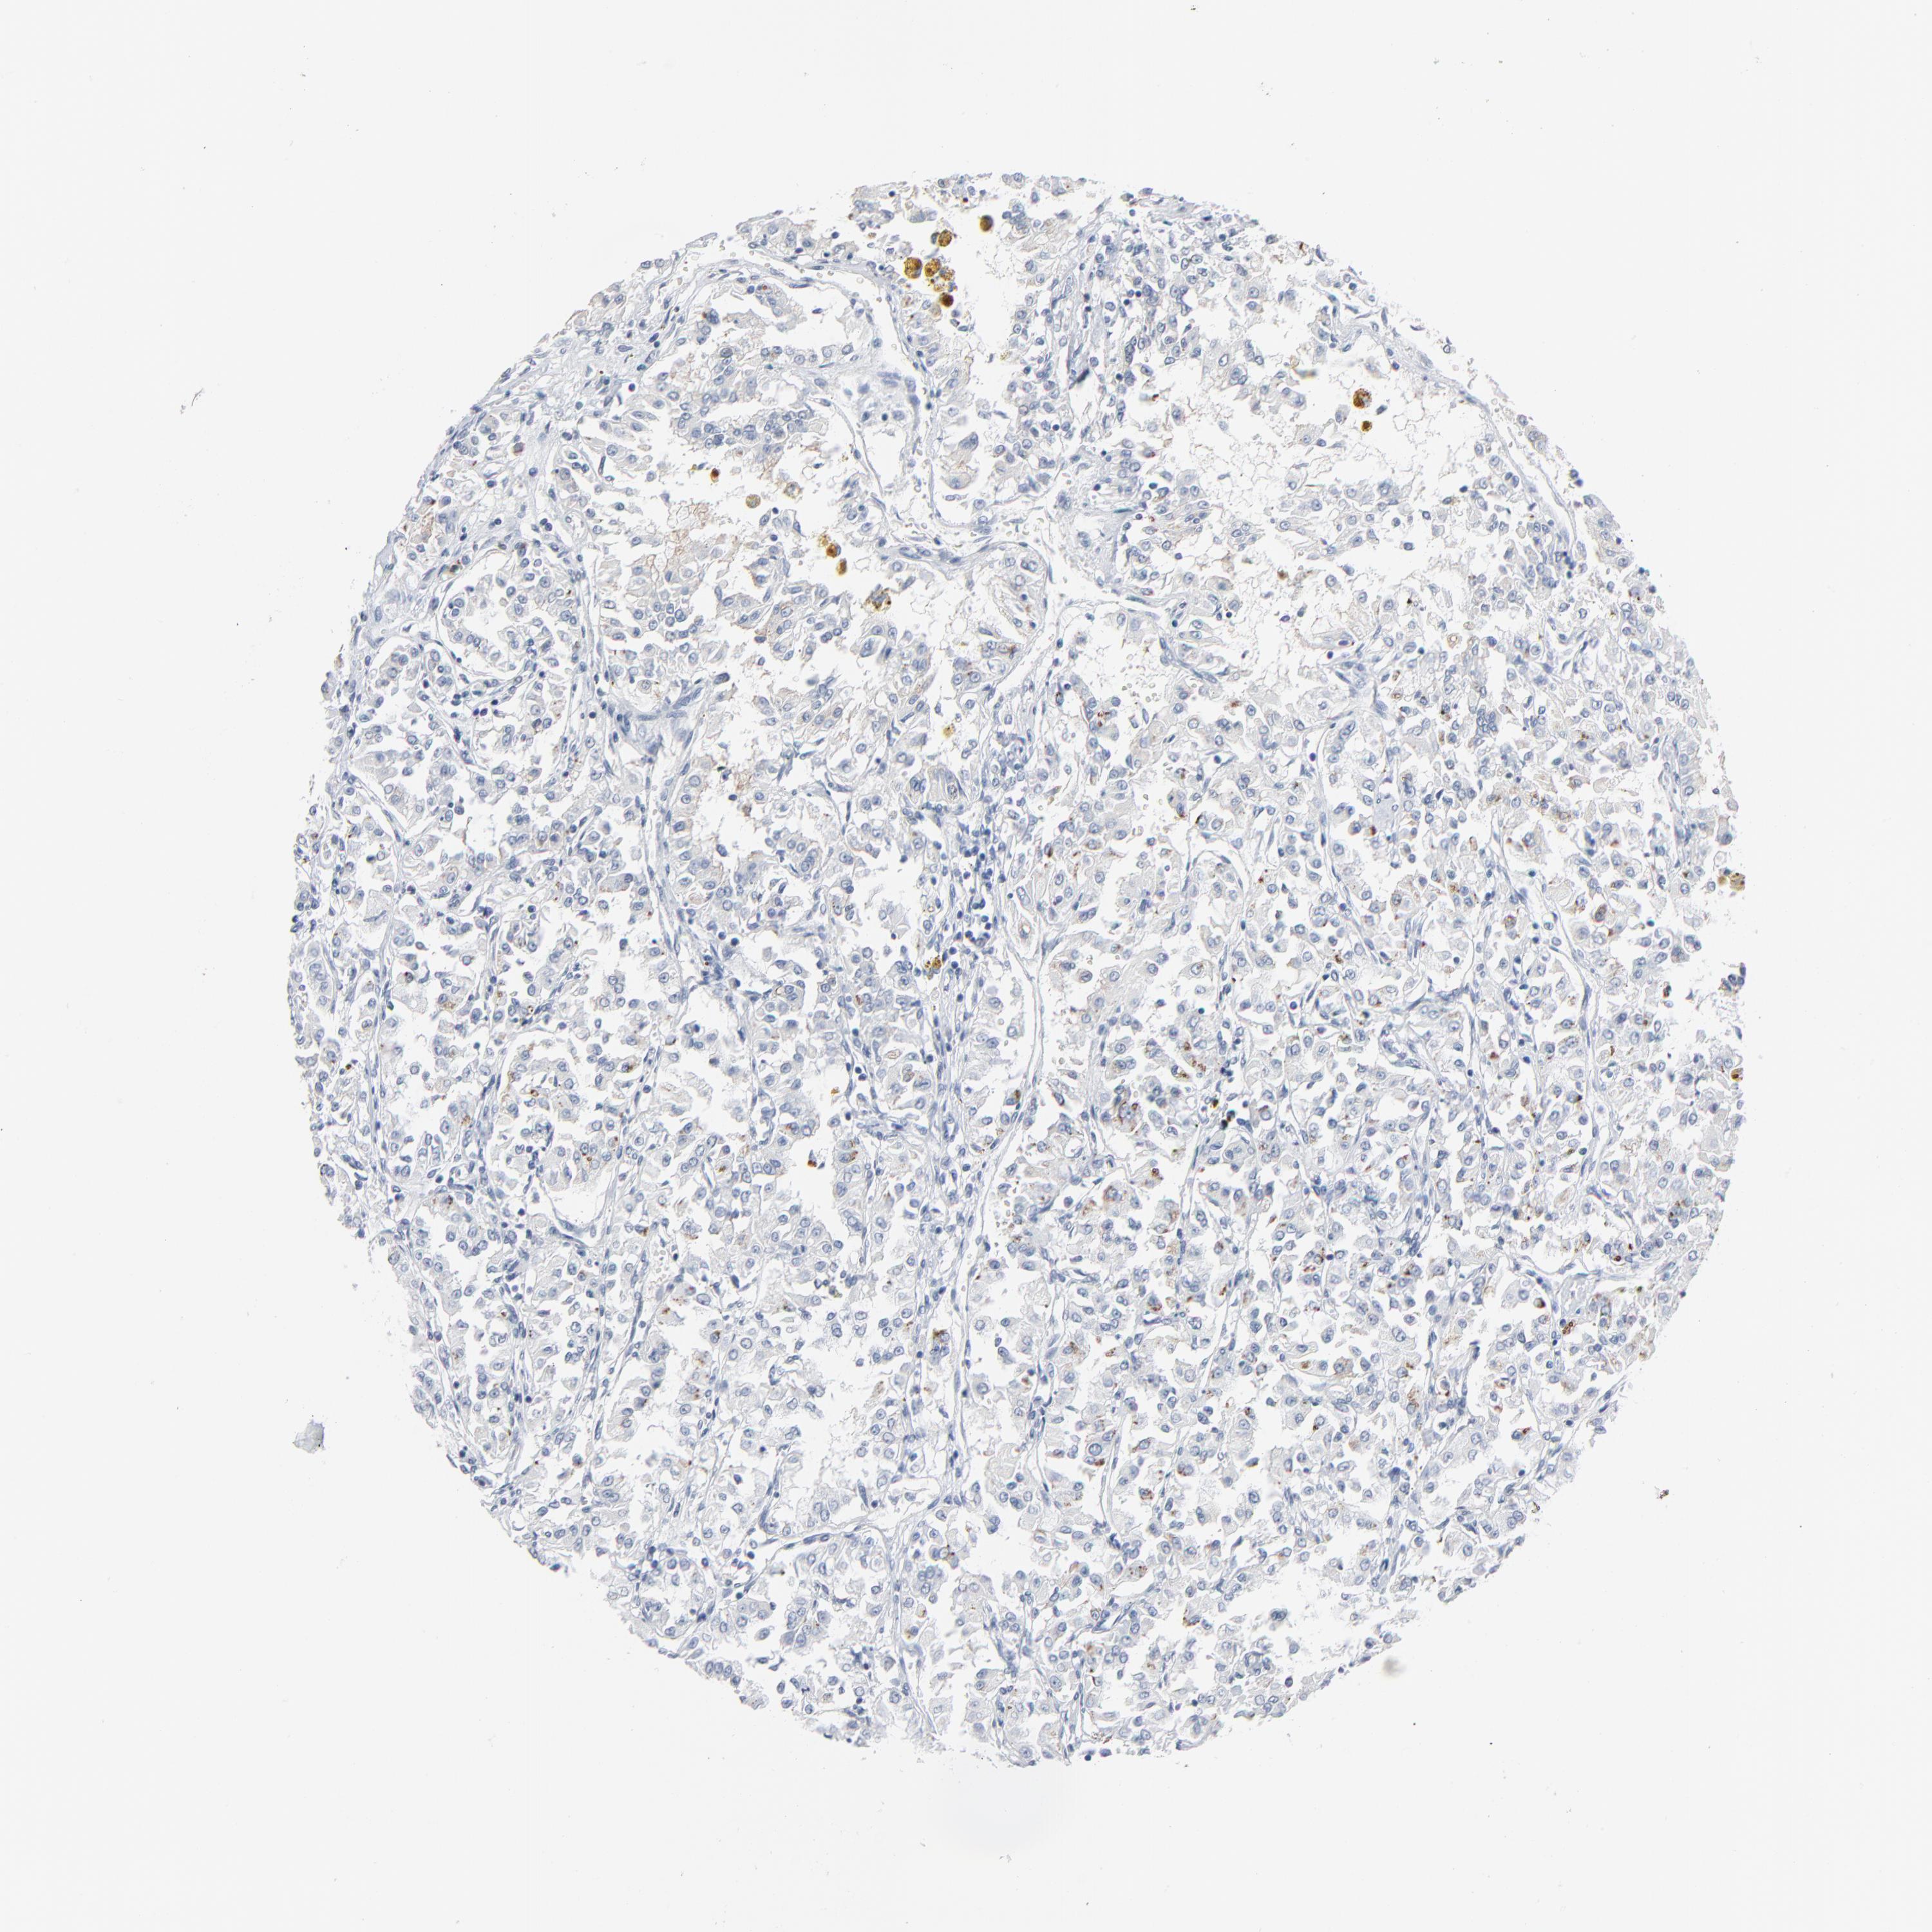

KIDNEY RENAL CLEAR CELL CARCINOMA (VALIDATION) - Interactive survival scatter ploti

The Survival Scatter plot shows the clinical status (i.e. dead or alive) for all individuals in the patient cohort, based on the same data that underlies the corresponding Kaplan-Meier plots. Patients that are alive at last time for follow-up are shown in blue and patients who have died during the study are shown in red.

The x-axis shows the expression levels (FPKM) of the investigated gene in the tumor tissue at the time of diagnosis. The y-axis shows the follow-up time after diagnosis (years). Both axes are complimented with kernel density curves demonstrating the data density over the axes. The top density plot shows the expression levels (FPKM) distribution among dead (red) and alive patients (blue). The right density plot shows the data density of the survived years of dead patients with high and low expression levels respectively, stratified using the cutoff indicated by the vertical dashed line through the Survival Scatter plot. This cutoff is automatically defined based on the FPKM cutoff that minimizes the p-score. The cutoff can be changed by dragging the vertical line or by entering a cutoff value in the square labeled "Current cut-off".

Under the Survival Scatter plot the p-score landscape (black curve; left axis) is shown together with dead median separation (red curve; right axis). Dead median separation is the difference in median mRNA expression between patients who have died with high and low expression, respectively. It is calculated as follows: median FPKM expression of dead patients with high expression - median FPKM expression of dead patients with low expression. This is intended to aid the user in visually exploring custom cutoffs and the associated p-scores and dead median separation.

Individual patient data is displayed and can be filtered by clicking on one or more of the category buttons on the top of the page. Categories describing expression level and patient information include: high, low, alive, dead, female, male and tumor stages. The scale of the x-axis can be toggled between linear and log-scale by clicking on the "x log" button. Mouse-over function shows TCGA ID, patient information and mRNA expression (FPKM) for each patient.

& Survival analysisi

Kaplan-Meier plots summarize results from analysis of correlation between mRNA expression level and patient survival. Patients were divided based on level of expression into one of the two groups "low" (under cut off) or "high" (over cut off). X-axis shows time for survival (years) and y-axis shows the probability of survival, where 1.0 corresponds to 100 percent.

PHGDH is not prognostic in Kidney Renal Clear Cell Carcinoma (validation)

Best expression cut offi

Based on the FPKM value of each gene, patients were classified into two groups and association between prognosis (survival) and gene expression (FPKM) was examined. The best expression cut-off refers the FPKM value that yields maximal difference with regard to survival between the two groups at the lowest log-rank P-value. Best expression cut-off was selected based on survival analysis .

When clicking on this number, the vertical dashed line indicating cut-off, the interactive survival plot, and the Kaplan-Meier curve will be adjusted to show results based on the best expression cut-off.

: 3.78

P scorei

Log-rank P value for Kaplan-Meier plot showing results from analysis of correlation between mRNA expression level and patient survival.

N/A

TCGA RNA samplesi

RNA-seq data is reported as average FPKM (number Fragments Per Kilobase of exon per Million reads), generated by the The Cancer Genome Atlas (TCGA) .

Normal distribution across the dataset is visualized with box plots, shown as median and 25th and 75th percentiles. Points are displayed as outliers if they are above or below 1.5 times the interquartile range. FPKM values of the individual samples are presented next to the box plot.

Average pTPM 21.4

Number of samples 100